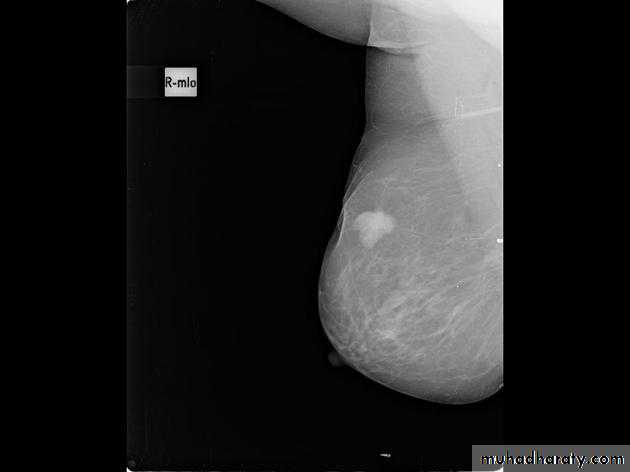

The mediolateral oblique (MLO) view is one of standard mammographic views. It is the most important projection as it allows to depict most breast tissue.

Mammography

The sensitivity of mammography for the detection of ILC reportedly ranges between 55-80% 8. Because of the limitations of mammography in detecting ILC, other modalities, such as sonography and MR imaging, are being used in evaluating clinically suspicious findings and known cancers to assess the extent of disease. ILC are more commonly seen on the craniocaudal (CC), compared to the mediolateral oblique (MLO).